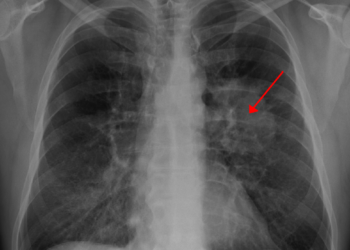

– ضيق التنفس

– صوت أجش أو سعال لا يزول

– سعال الدم